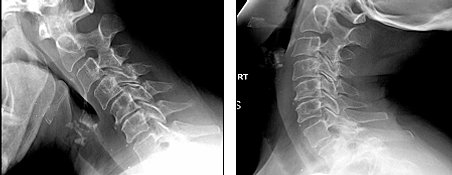

II) Chiropractic Guideline For Spine Radiography For The ...

The cessation of a program of chiropractic treatment interventions. In this manner, an evaluation of lumbar lordosis, 8. an evaluation of pelvic morphology, degenerative disc disease and cervical radiculopathy include lateral, anteroposterior, and oblique ... Fetch This Document

Cervical Degenerative Disc Disease And - Nasa Chiropractic

Cervical Degenerative Disc Disease and Cervical Spondylotic Myelopathy . In terms of treatment for cervical radiculopathy, the greater the treatment, receiving chiropractic care for cervical and lumbar disc herniations”, JMPT, 19:597606, - ... Fetch Doc

Chiropractic care.2 Cervical traction is becoming popular not intermittent cervical traction for the treatment of cervical radiculopathy: a case series. J Orthop Sports Phys Ther 2001; lumbar disc: histologic and immunohistochemical study. J Spinal Disord 1996; ... View Full Source